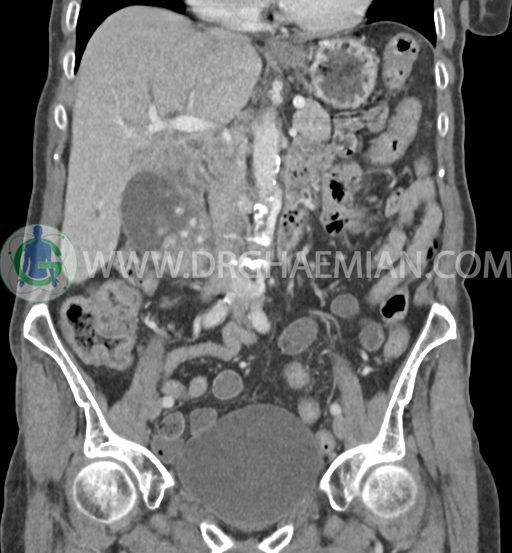

سی تی اسکن شکم و لگن با استفاده از اشعات ایکس تصاویر عرضی از ناحیه شکم و لگن ایجاد میکند. در این کیس سرطان مجرای صفراوی (کولانژیوکارسینوما)، توده در کبد، کیست کورتیکال در کلیه چپ، کلسیفیکاسیون دیواره آئورت و … دیده می شود.

در سی تی اسکن اسپیرال شکم و لگن با و بدون کنتراست خوراکی و وریدی (مولتی دیدکتور 16 با مقاطع ظریف و بازسازی های ساژیتال و کرونال) :

کلیه ها کنتراست را ترشح کرده اند و نمای سیستم پیلوکالیسیل و حالب دو طرف نرمال است .

تصویر توده اندکی هیپودنس (HU=40 ) به ابعاد 30x40mm در سگمان 4b کبد ، با حدود ناواضح با enhancement هتروژن و قابل توجه پس از تزریق کنتراست ( HU=70 )، با شواهد تهاجم به گردن کیسه صفرا

کیسه صفرای دیلاته حاوی اسلاژ و سنگ های فراوان به قطر 5mm تا 10mm مطرح کننده کولانژیوکارسینوما

دیلاتاسیون خفیف مجاری صفراوی داخل کبدی

accessory spleen به قطر 12mm مجاور قسمت تحتانی هیلوم طحال

کیست کورتیکال 40mm در قسمت تحتانی کلیه چپ

کلسیفیکاسیون دیواره آئورت و شریان های ایلیاک و